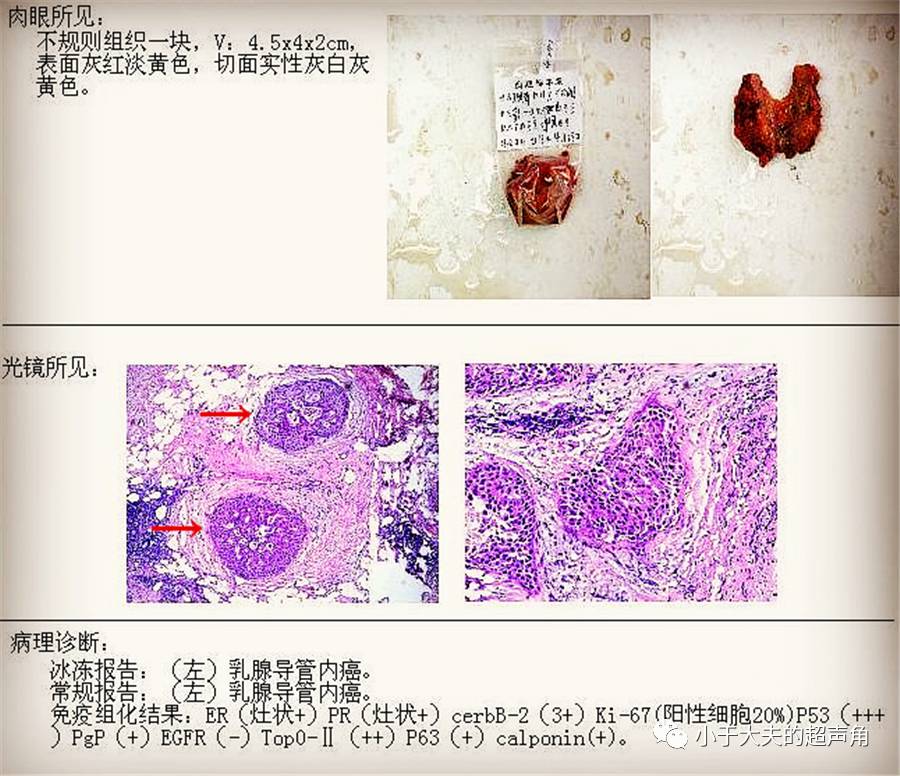

【图片】转移性乳腺癌病理学图片_圈子_医脉通

揭秘:这乳腺究竟是怎么啦? ~ “呆在原处的导管癌” DCIS之粉刺癌